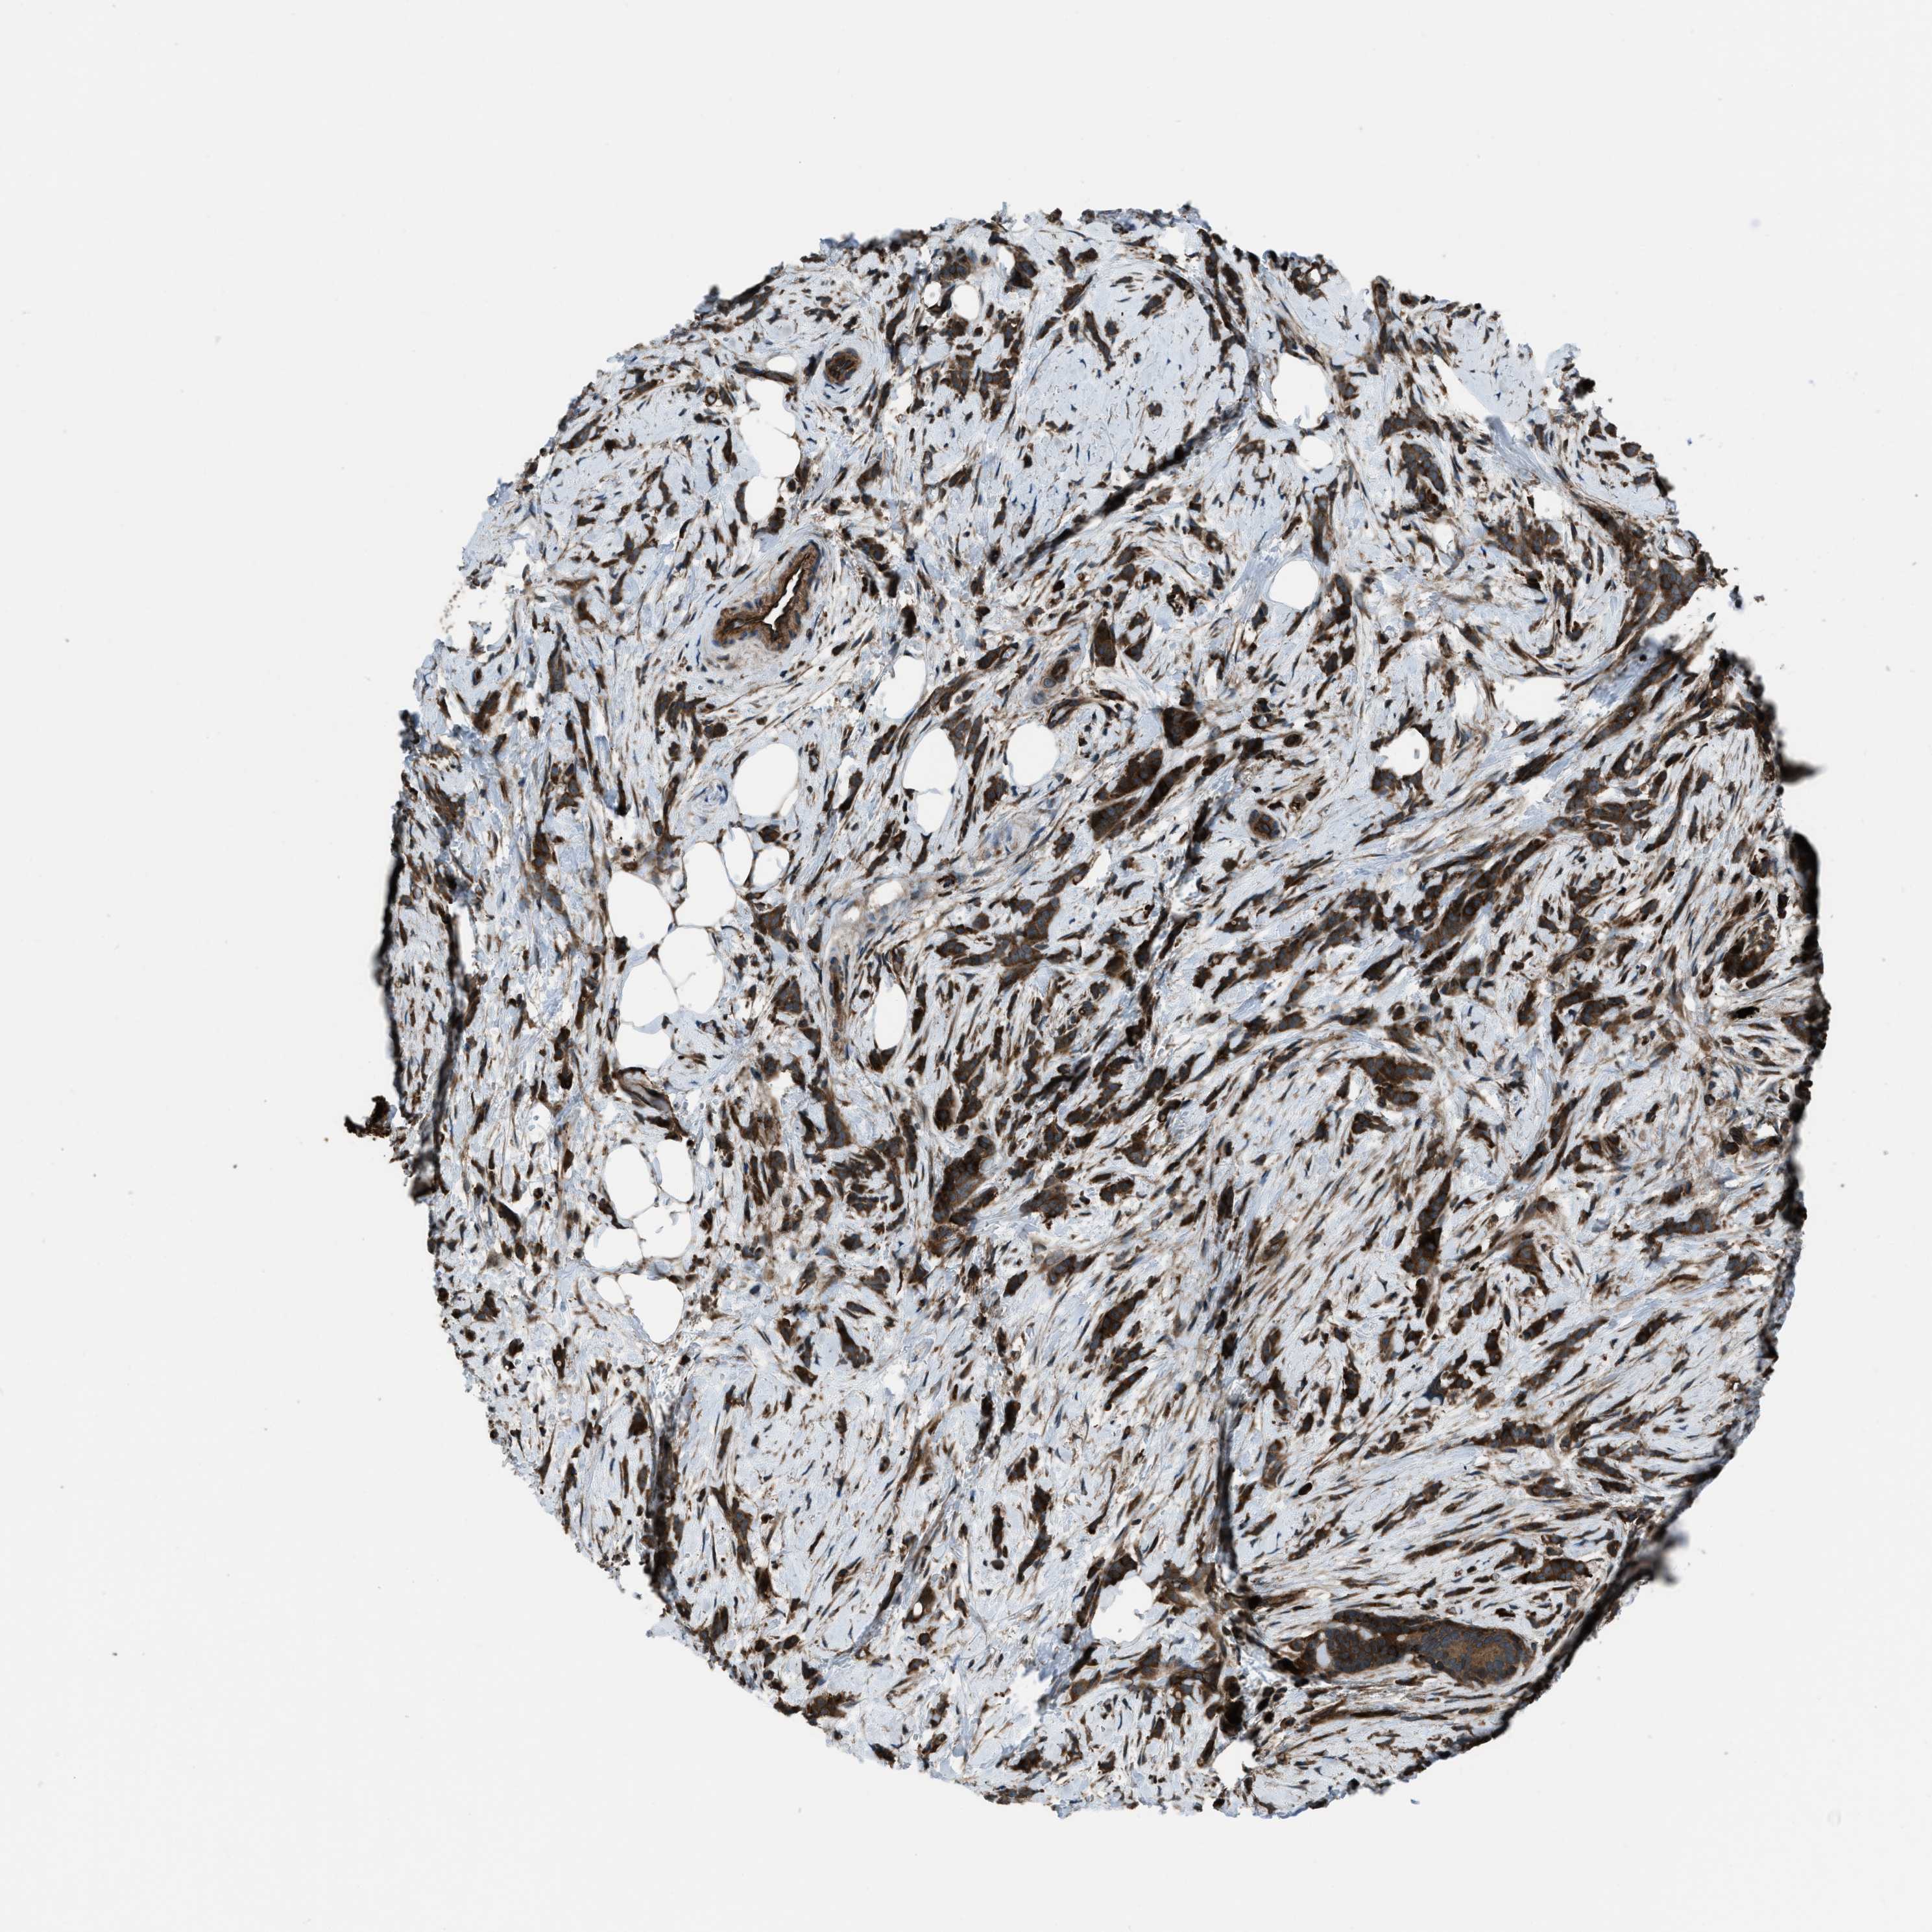

CANCER BREAST CANCER Show tissue menu

BRCA TCGA BRCA VALIDATION PROTEIN EXPRESSION